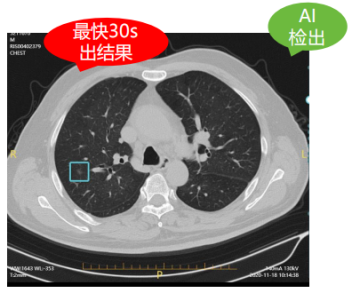

以肺結(jié)節(jié)人工智能篩查為例,正常的一個肺部CT平掃檢查具有幾百張片層,而一位熟練的診斷醫(yī)生想要從這些復(fù)雜的影像中發(fā)現(xiàn)并診斷病灶可能需要花上20-30分鐘,甚至是更長時間。而通過AI智能影像輔助診斷技術(shù)的精準(zhǔn)定位與檢測,自動檢出實(shí)性、磨玻璃、鈣化以及混合結(jié)節(jié)、疑似腫塊等,僅需30秒便可自動生成結(jié)構(gòu)化影像報告供醫(yī)生審查,雙肺結(jié)節(jié)檢出率高達(dá)99.64%!對0.5mm的微小結(jié)節(jié)都能瞬間定位,快速標(biāo)記結(jié)節(jié)大小、密度,并初步分辨良惡性,有效幫助醫(yī)生更加精準(zhǔn)篩查肺結(jié)節(jié),使肺癌患者及早得到良好診治。